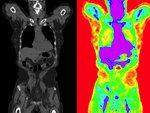

this is the follow-up exam, i.e. the moving image, to be aligned with the baseline

moving image

follow-up PET/CT